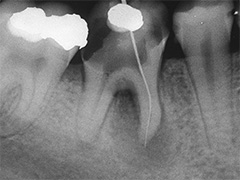

Der umfangreiche kariöse Defekt steuerte sehr bald hin auf die komplette Entfernung des Zahninnen­gewebes mit anschliessendem medikamentösen Wiederverschluss. Aufbissempfindlichkeit am Folgetermin ist immer Aufforderung zur erneuten Intensivsuche nach weiteren Kanälen, die hier einen 4. Ast zum Vorschein brachte. Nach 2 ausgelassenen Terminen

waren vorrangig Wiederherstellung von desinfizierender Einlage und provisorischer Füllung angezeigt. Eine weitere Woche später wurde in allen Kanälen das Medikament durch die endgültige Verschlussmasse ersetzt, worauf Zahn 36 mit 12-tägiger Verzögerung erneut zu rebellieren begann. Das hiess aus den hinteren Wurzeln Füllmaterial wieder raus und

Einlage erneut rein. Als es dann 4 Wochen später bei der hinteren Wur­zel aussen anzuschwellen begann und ein Medikamentenwechsel ohne Wir­kung blieb, wurden die hinteren Ka­näle abgefüllt und auch in gleicher Sitzung das überstopfte Material (Bild 1) mittels Resektion (Bild 2) von aussen entfernt.

Die ersten beiden Aufnahmen sind aus dem Jahr 1999, die 3. von 2006